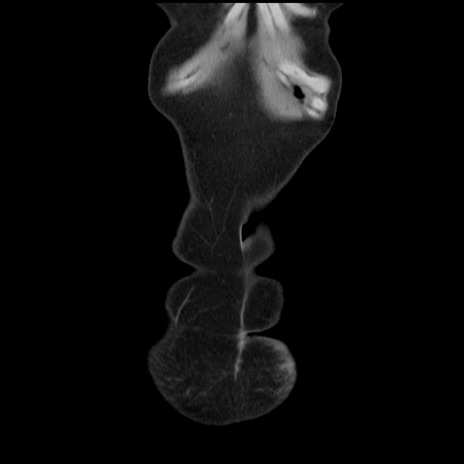

矢状断像